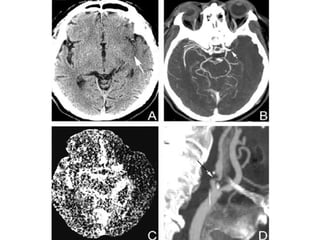

Circulação Anterior Compreende Carótida Interna e seus ramos Oclusão pode ser Intrínseca ex: aterosclerose, dissecção Embólica ex: FA, estenose carótida Cada artéria em manifestações distintas ACM ACA A Coroidal Anterior A Carótida Interna

Artéria Cerebral Média Mais comum devido êmbolos Aterosclerose pode causar êmbolos distais Menos comumente AIT de baixo fluxo Freqüentemente colaterais previnem estenose assintomática Os ramos corticais da ACM suprem a superfície lateral do hemisfério cerebral, exceto: polo frontal e uma faixa junto do bordo superomedial dos lobos frontais e parietais (ACA) Superfície inferior dos polos temporais e occipitais (ACP)

Artéria Cerebral Média ACM proximal Ramos penetrantes – a. lenticuloestriadas suprem putamen, globo pálido externo, cápsula interna posterior, coroa radiata adjacente, núcleo caudado ACM subdivide-se na fisura de Sylvian Superior : frontal e parietal superior Interior: temporal e parietal inferior

Artéria Carótida Interna Quadro clínico varia se a isquemia é causada por trombo, êmbolo ou baixo fluxo. O córtex suprido pela ACM é o mais afetado Se C.Willis patente, oclusão pode não ser notada Se trombo propaga ou emboliza p/ ACM, clínica de ACM Algumas vezes infarto maciço – córtex e subst. Branca Se ACM e ACA: abulia, estupor, hemiplegia, hemianestesia, afasia ou anosognosia. Se ACP for ramo da ACI (ACP fetal), sintomas de AVC posterior

Circulação Posterior Formada por: Duas Artérias Vertebrais Junção pontomedular A Artéria Basilar Fossa Interpeduncular Duas ACP Essas artérias dão origem a Ramos circunferenciais longos e curtos Ramos penetrantes profundos Cerebelo Medula Ponte Bulbo  Subtálamo Tálamo Hipocampo Lobo Occipital Lobo Temporal Medial A oclusão de cada ramo produz sua própria síndrome

Artéria Cerebral Posterior 75%: ambas da Art. Basilar 20%: uma origina-se da ACI ipsilateral, via A. Comunicante Posterior 5%, ambas originam-se da ACI ipsilateralmente (Segmento P1 atresico) As síndromes geralmente originam-se de ateromas ou êmbolos; pode também ser causado por dissecção e displasias fibromusculares. São duas: P1 síndrome : sinais mesencefálicos, subtalâmicos e talamicos – P1 proximal e ramos penetrantes P2 síndrome : sinais corticais temporais e occipitais - P2 distal à junção da ACP com A. Comunicantes Posteriores.